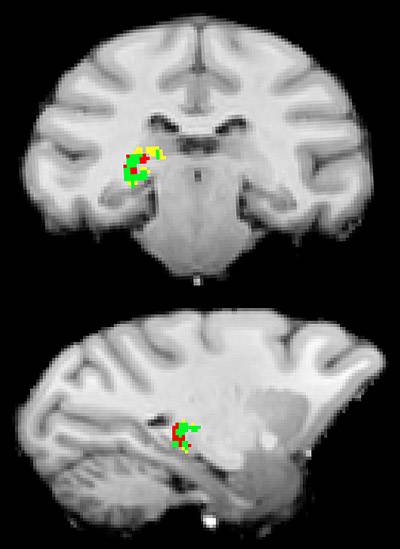

Princeton University researchers have found that the pulvinar, a mysterious region deep in the human brain, acts like a switchboard operator to make sure that separate areas of the brain are communicating about the same external information most important to our behavior at a given moment. The pulvinar uses electrical impulses to synchronize and allow more effective communication between brain cells in the visual cortex, which processes visual information. The researchers produced neural connection maps that show the pulvinar's connection to these brain regions. In this scan, the pulvinar communicates with the occipital lobe (yellow) and the temporal lobe (red) individually, and with both (green). Image courtesy of Science/AAAS